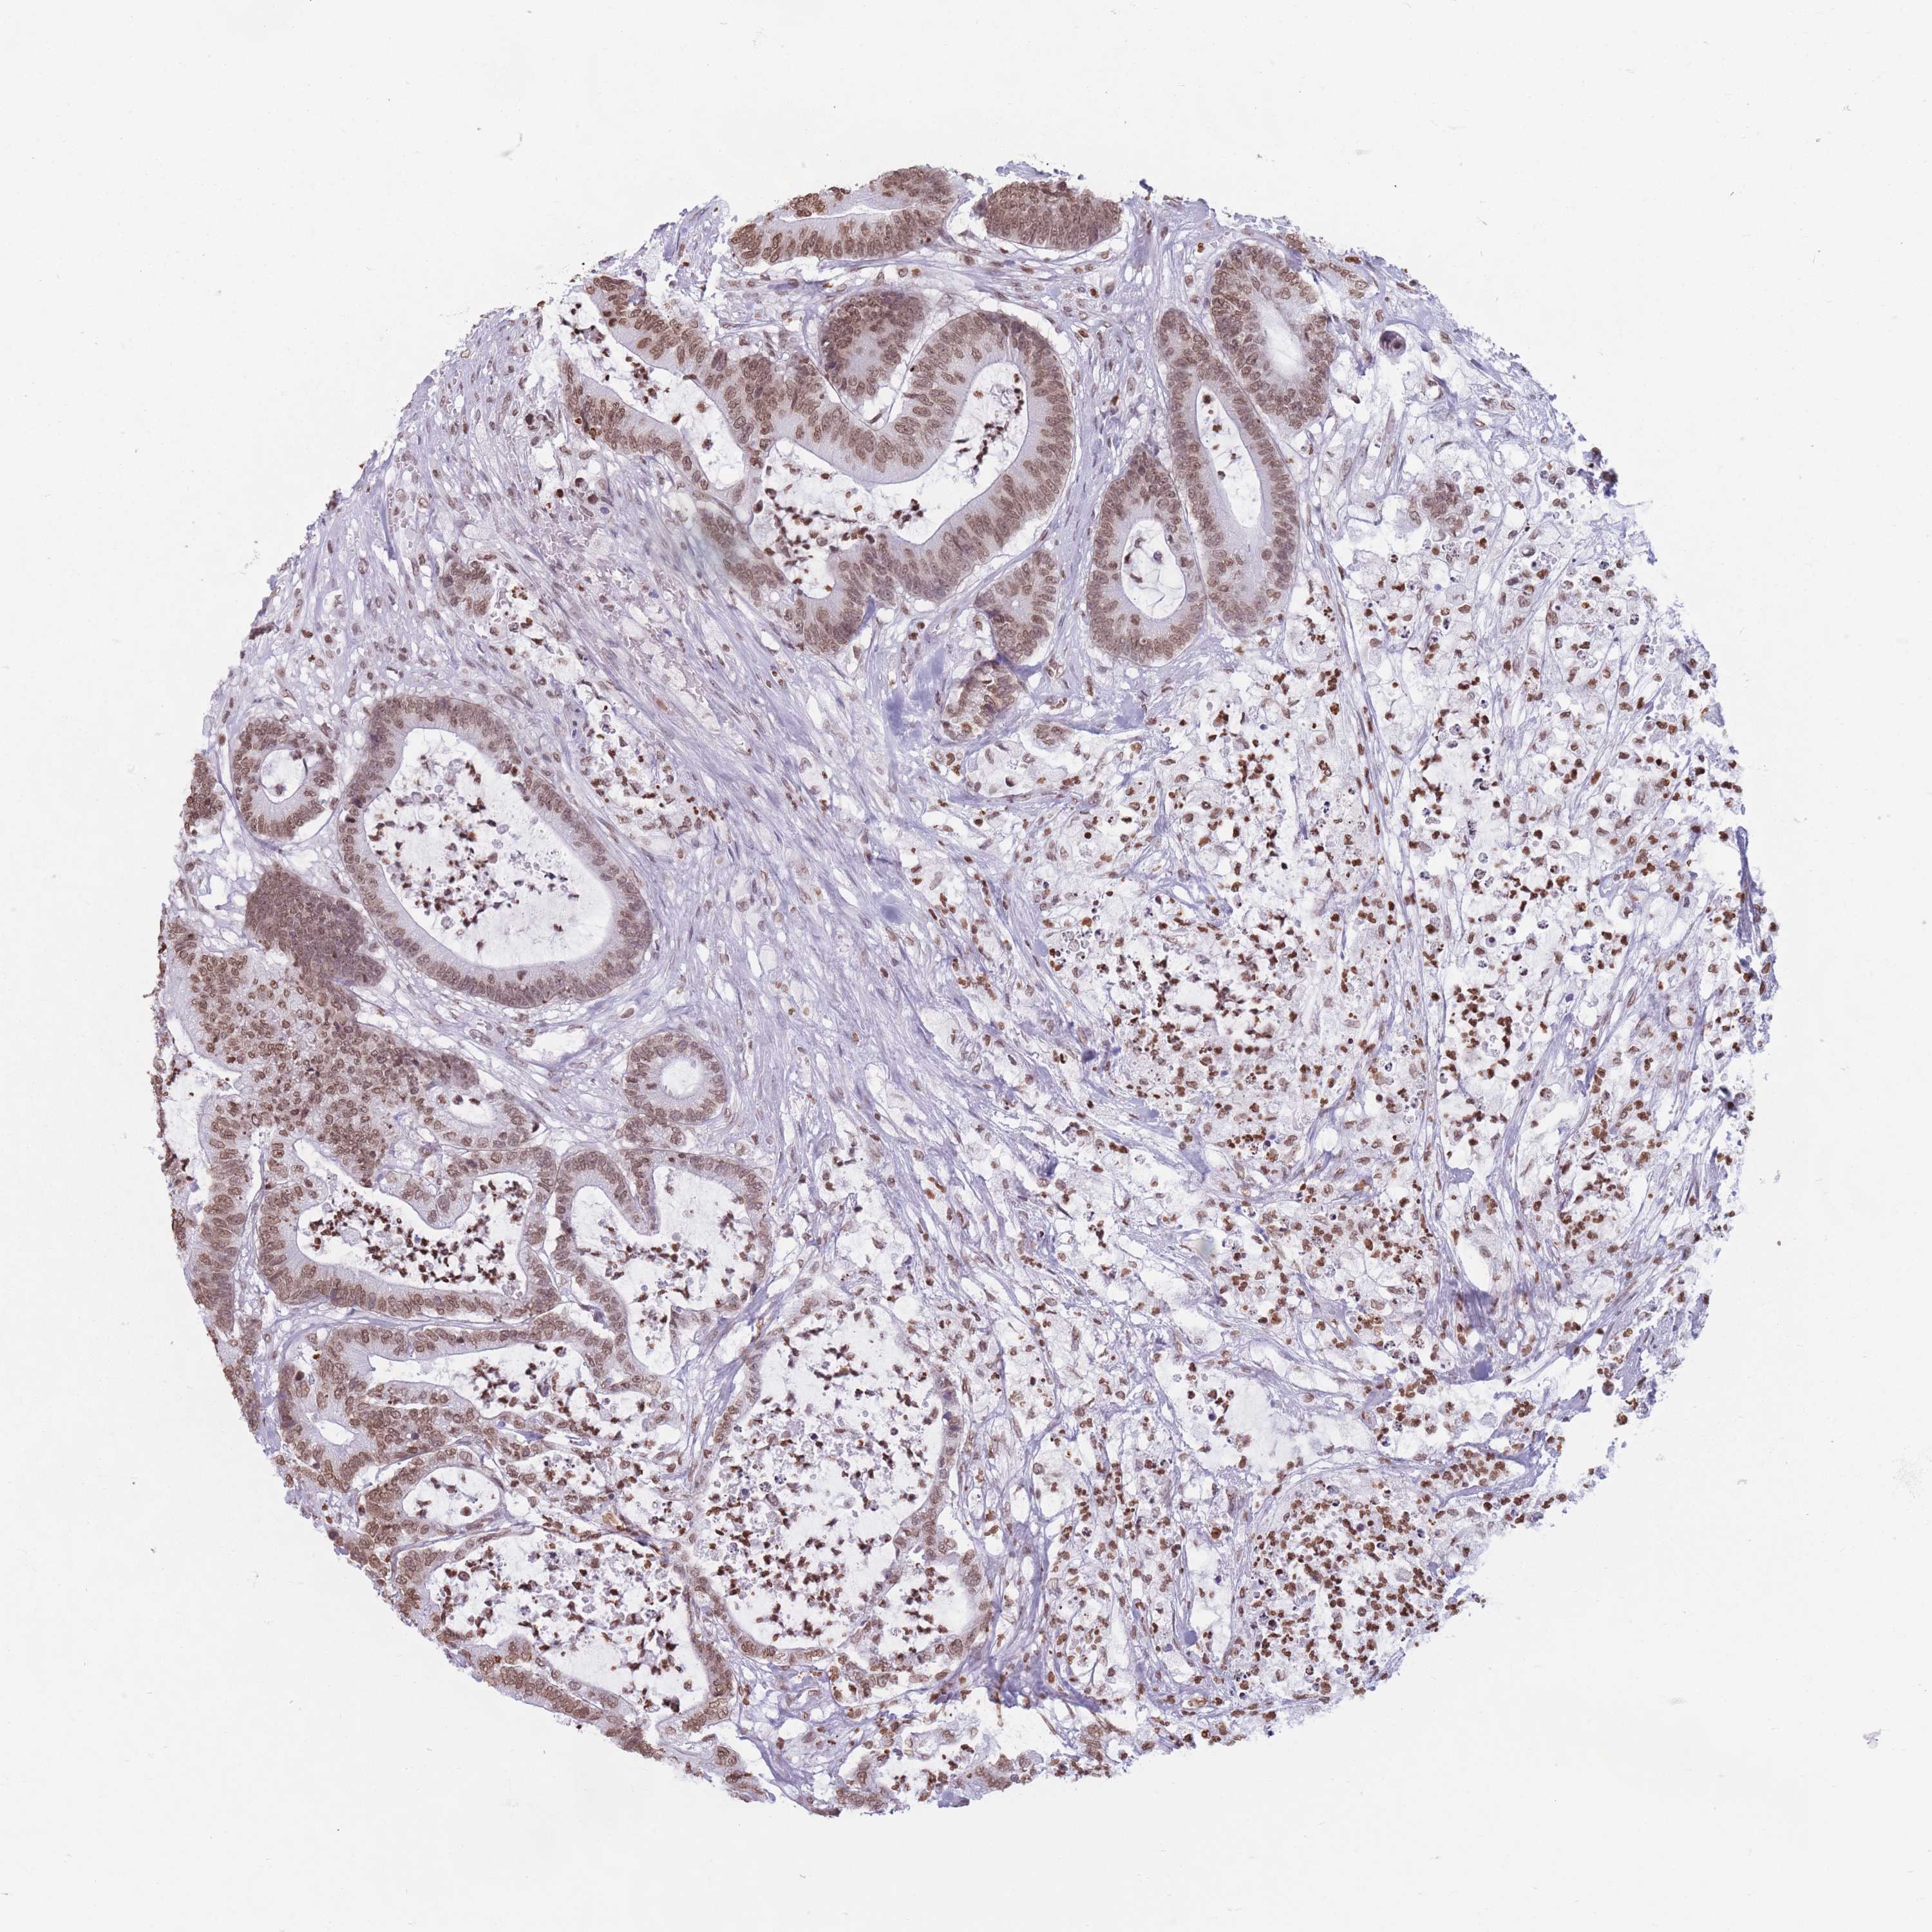

CANCER COLORECTAL CANCER Show tissue menu

COAD TCGA COAD VALIDATION READ TCGA READ VALIDATION PROTEIN COAD CPTAC PROTEIN EXPRESSION

ANTIBODIES

AND

VALIDATION